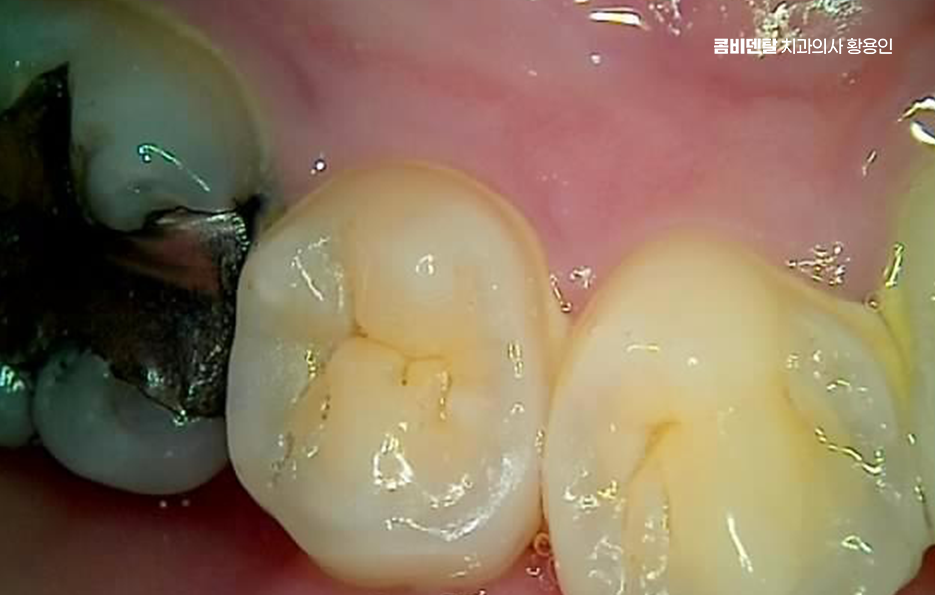

이처럼 오래된 아말감이 노후되고 문제가 되어 교체하는 사례가 많은데 사실 아말감 뿐 아니라 모든 보철물은 수명이 있고 교체 주기가 있기 때문에 오래된 보철물은 정기적으로 검진하여 필요 시에는 늦지 않게 교체, 재치료를 받는 것이 자연치아를 보존하는 중요한 대처가 될 수 있는데요

지금과 달리 예전에는 충치 치료라고 하면 거의 아말감으로 떼우는 게 기본이었는데 지금은 소재도, 기술도 발전하면서 상황이 달라졌어요. 하지만 여전히 예전에 치료했던 아말감이 입 안 어딘가에 남아 있는 경우가 많고 겉보기에는 튼튼해 보일 수 있지만, 오래된 아말감은 내부에서 골치 아픈 문제가 자라고 있을 수도 있었어요

아말감 교체 레진 인레이와 같은 재치료를 고려하게 되는 두 번째 문제는 변색으로 아말감이 들어간 치아는 시간이 지날수록 잿빛이나 회색으로 변할 수 있는데 잇몸이 어두워지거나, 치아 전체가 탁한 색으로 보이는 일이 생길 수 있으며 어금니라도 웃거나 말할 때 드러나는 위치면 보기에도 좋지 않겠고 심미적인 부분이 중요해진 요즘 시대에는 충분히 재치료를 고민할 수밖에 없는 이유가 되는 거예요.